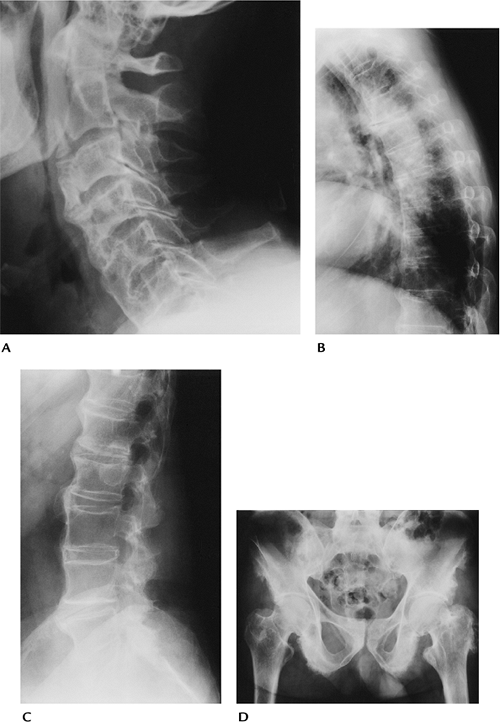

|

FIGURE 15-44 DISH. (A)

Lateral view of the cervical spine with prominent anterior ossification causing dysphagia. The disc spaces are preserved and at least four segments are involved. (B) Lateral radiograph of the thoracic spine with flowing osteophytic ossification and preserved disc spaces. (C) Lateral view of the lumbar spine with anterior ossification and normal disc spaces. (D) AP radiograph of the pelvis with ischial whiskering and prominent enthesophytes, especially on the left greater trochanter. |